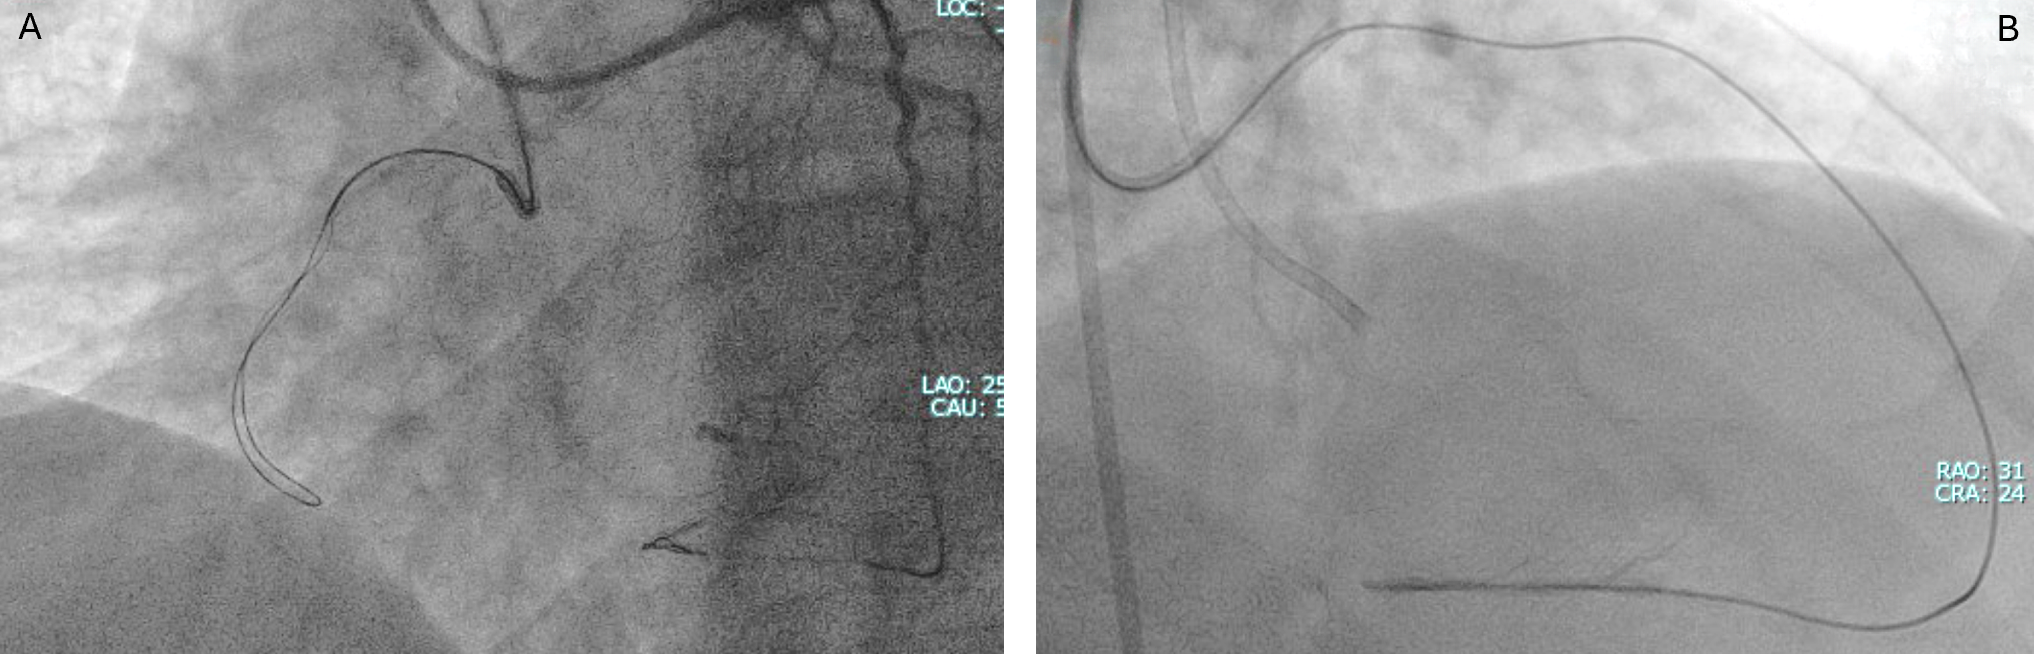

A primary retrograde strategy was selected but septal collateral wiring was unsuccessful. Epicardial collaterals from the LAD were subsequently crossed (Figure 2, Video 2); however, a retrograde wire (Confianza Pro 12; ASAHI INTECC) failed to puncture the distal cap. Antegrade wire (Gladius MG; ASAHI INTEC) knuckle was used until just before it reached the distal cap (Figure 3, Videos 3 and 4). A 3.0 x 20-mm TREK balloon (Abbott) was delivered retrogradely through the epicardial collateral and inflated at the bifurcation (Video 5). Next, an antegrade wire (Gladius EX; ASAHI INTECC) was delivered into the distal true lumen of the posterior descending artery (Figure 4, Video 6). The RCA was successfully stented with an XIENCE Pro drug-eluting stent (Abbott), with restoration of Thrombolysis in Myocardial Infarction 3 flow (Figure 5, Video 7).